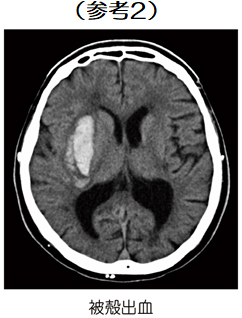

52歳の男性。左上下肢麻痺を認める。頭部CTの水平断像を示す。 病変がみられるのはどれか。

診断:視床出血

視床出血